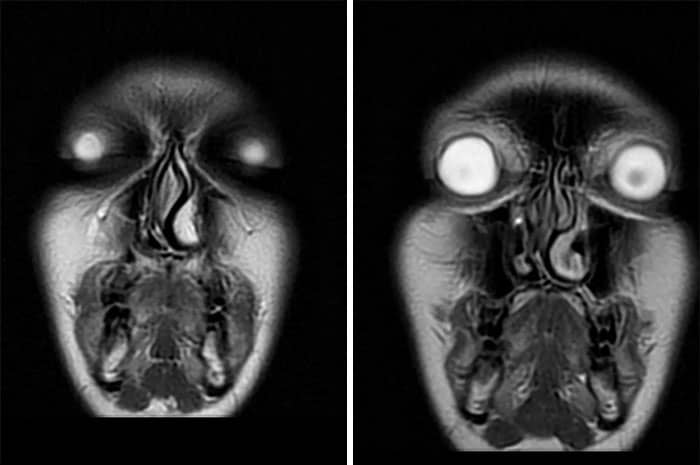

#39 My Mri Pictures Are Straight Up Nightmare Fuel